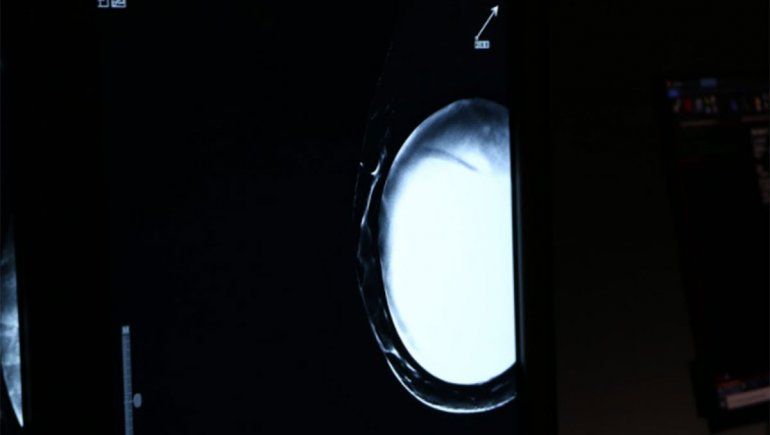

Lancioni destacó que, en este contexto, es necesario llevar tranquilidad a las pacientes y no alertar ante “falsos positivos” en mamografías. La recomendación es esperar tres meses después de la inmunización contra el coronavirus y realizar un nuevo control de seguimiento.

Una manera de evitar el problema sería posponer las mamografías rutinarias y otras pruebas de escaneo durante al menos seis semanas después de la última dosis de la vacuna, según un artículo de un grupo de expertos en la revista Radiology, publicado días atrás.

Por eso desde la Sociedad de Imágenes del Seno, en Estados Unidos, sugieren como una pauta en pandemia, que las mamografías de detección (mamografías anuales regulares para pacientes sin síntomas) deben programarse antes de la primera dosis de una vacuna COVID-19 o de cuatro a seis semanas después de la segunda.